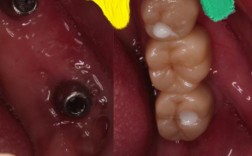

针对牙种深了,处理方法需根据发现时机和严重程度制定:

术中处理:手术过程中若发现种植体植入过深,应立即停止操作,若偏差较小(如1-2mm),且未触及重要解剖结构,可通过选择高基台或调整修复体边缘位置补偿;若偏差较大(超过2mm)或已压迫神经、穿透窦腔,需取出种植体,重新备洞调整位置,必要时结合引导骨再生技术(GBR)补充骨量,确保种植体位于理想位置(通常下颌种植体尖端应距离下颌管2mm以上,上颌应距离上颌窦底1-2mm)。